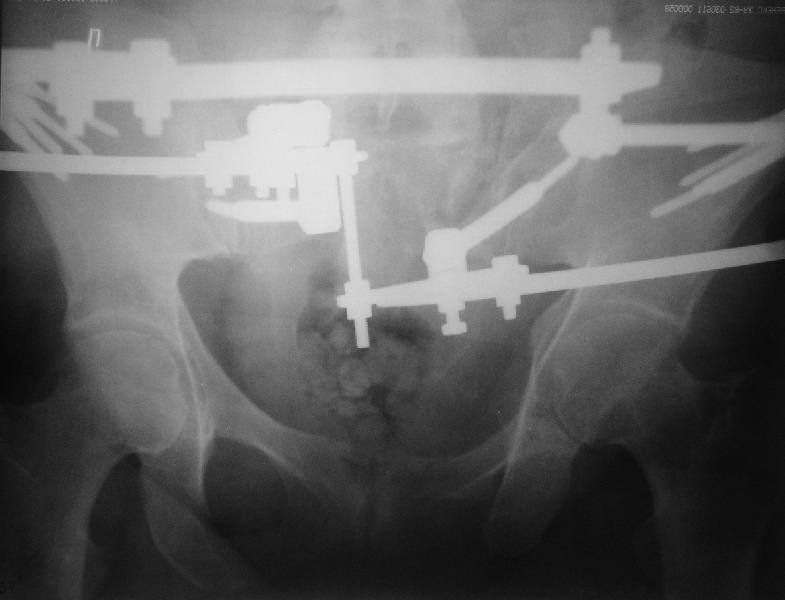

Прооперировали молодую девушку 32 лет спустя 9 мес после травмы. Имелся стойкий болевой синдром, неопороспособность левой н/конечности, моторные и сенсорные нарушения в левой голени и стопе, патологическая подвижность левой половины таза. Первым этапом закрыто в аппарате исправили деформацию ( в течении 2,5 нед). Вторым закрытое введение илиосакральных винтов в крестец (канюллированные 7,2 мм Chm) + туннелизация зоны псевдоартроза спицама Киршнера, реконструкция передних отделов таза, накостный остеосинтез . Аппарат частично демонтирпован, оставлена "передняя рама" После устранения деформации отмечен регресс неврологической симптоматики, уменьшение болевого синдрома. Интересующие вопросы: 1. Прогноз для сращения псевдоартроза крестца. 2. сроки нагрузки весом левой половины таза. Буду очень признателен за ваши мнения по этому поводу.A female 32 y.o. admitted to our unit 9 months after initial injury with pain, inability to bear weight at the left lower limb, sensor and motor disturbances in the left foot and tibia, with mobility of the left hemipelvis.At first closed reduction was performed by an external fixator within 2,5 weeks. After correction her pain decreased and some neurological progress was achieved. Now two iliosacral screws 7,2 mm were inserted, and anterior lesion was fixed by a plate. External fixator was partially unmounted, only anterior frame left in place.Images attached.How would you evaluate chances of healing of the sacrum with the current position?When would you allow weight-bearing of the left leg?THX in advance.